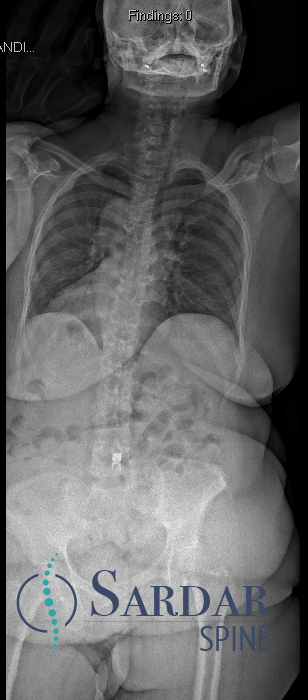

From robotics and AI-driven surgical planning to virtual modeling and custom implants, I’ve embraced a combination of tools that allow me to create tailored surgical plans for my patients—particularly those with scoliosis and spinal deformities.

What sets my approach apart is the seamless integration of these advanced technologies to ensure unparalleled accuracy and better outcomes for each patient.